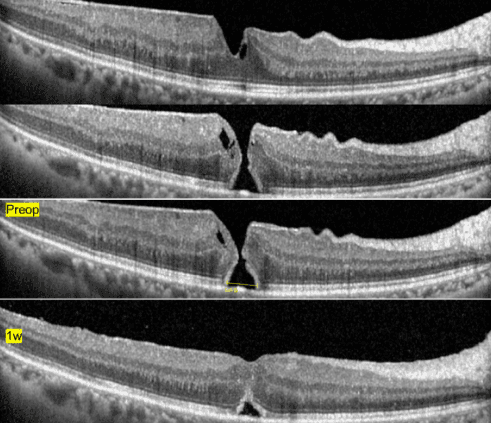

정밀 진단 (OCT)

빛간섭단층촬영(OCT)은 황반원공 진단의 핵심입니다.

CT처럼 눈 속을 들여다봅니다.

망막의 단면을 마이크로미터 단위로 촬영하여 원공의 크기, 깊이, 견인 상태, 망막 층의 손상 정도를 정확하게 파악합니다. 수술 여부와 예후를 결정하는 가장 중요한 검사입니다.

- 원공의 크기 측정

- 유리체 견인 유무 확인

- 망막 부종 동반 여부 확인